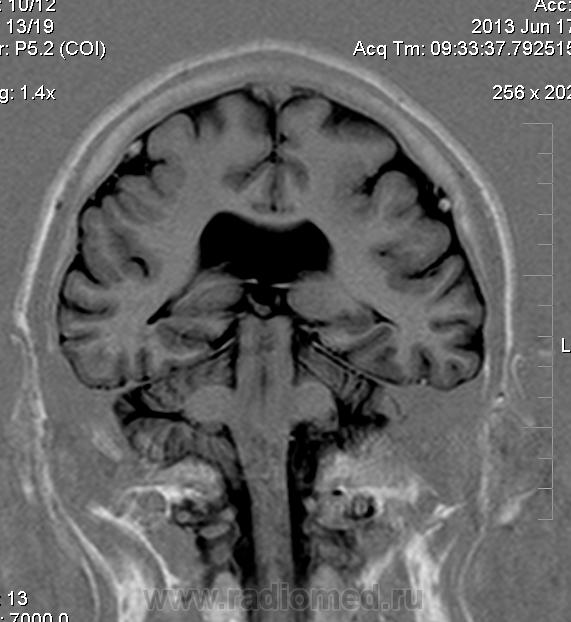

Мужчина 32 лет. Из анамнеза: перинатальное повреждение ЦНС, ДЦП, дизартрия, правосторонний верхний монопарез. С 16 лет приступы эпилепсии.

Аплазия прозрачной перегородки. Шизэнцефалия с открытыми краями в лобно-теменной области слева. Шизэнцефалия с закрытыми краями в лобной области справа? Утолщение коры по контуру расщелин и в области глазничной извилины правой лобной доли. Микрогирия? Гиперостоз костей свода черепа. Уважаемые коллеги, возможно я ошибаюсь, или есть еще аномалия?

Спасибо. Как тогда лучше сформулировать заключение? МР-картина кортикальной дисплазии : двусторнняя шизэнцефалия с утолщением коры по контуру расщелин, микрогирия в лобной области справа, очаг гетеротопии серого вещества в области  глазничной извилины правой лобной доли. Признаки септооптической дисплазии (гипоплазия зрительных нервов, аплазия прозрачной перегородки). Лиссэнцефалии не вижу. Есть сомнения по поводу шизэнцефалии справа (может быть я запуталась в микрогирии и мерещится шизэнцефалия?) Нет ли какой либо анамалии развития черепа?

На мой взгляд, полимикрогирия двусторонняя (конвекситальные отделы дорзальных отделов лобных долей и частично теменных, а также в базальном отделе полюса правой лобной доли) + закрытая шизенцефалия левой лобно-теменной области. Аплазия прозрачной перегородки (как признаки лобарной голопрозенцефалии).